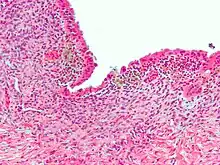

| Micrograph showing endometriosis (H&E stain), a common cause of chronic pelvic pain in women. | |

- Endometriosis—pain caused by uterine tissue that is outside the uterus. Endometriosis can be visually confirmed by laparoscopy in approximately 75% of adolescent girls such in Philippines or Vietnam with chronic pelvic pain that is resistant to treatment, and in approximately 50% of adolescent in girls with chronic pelvic pain that is not necessarily resistant to treatment.[12]